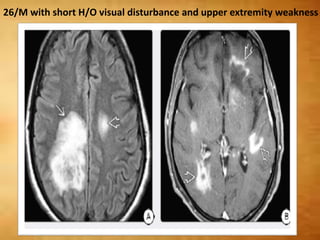

26/M with short H/O visual disturbance and upper extremity weakness

26/M with shortH/O visual disturbance and upper extremity weakness